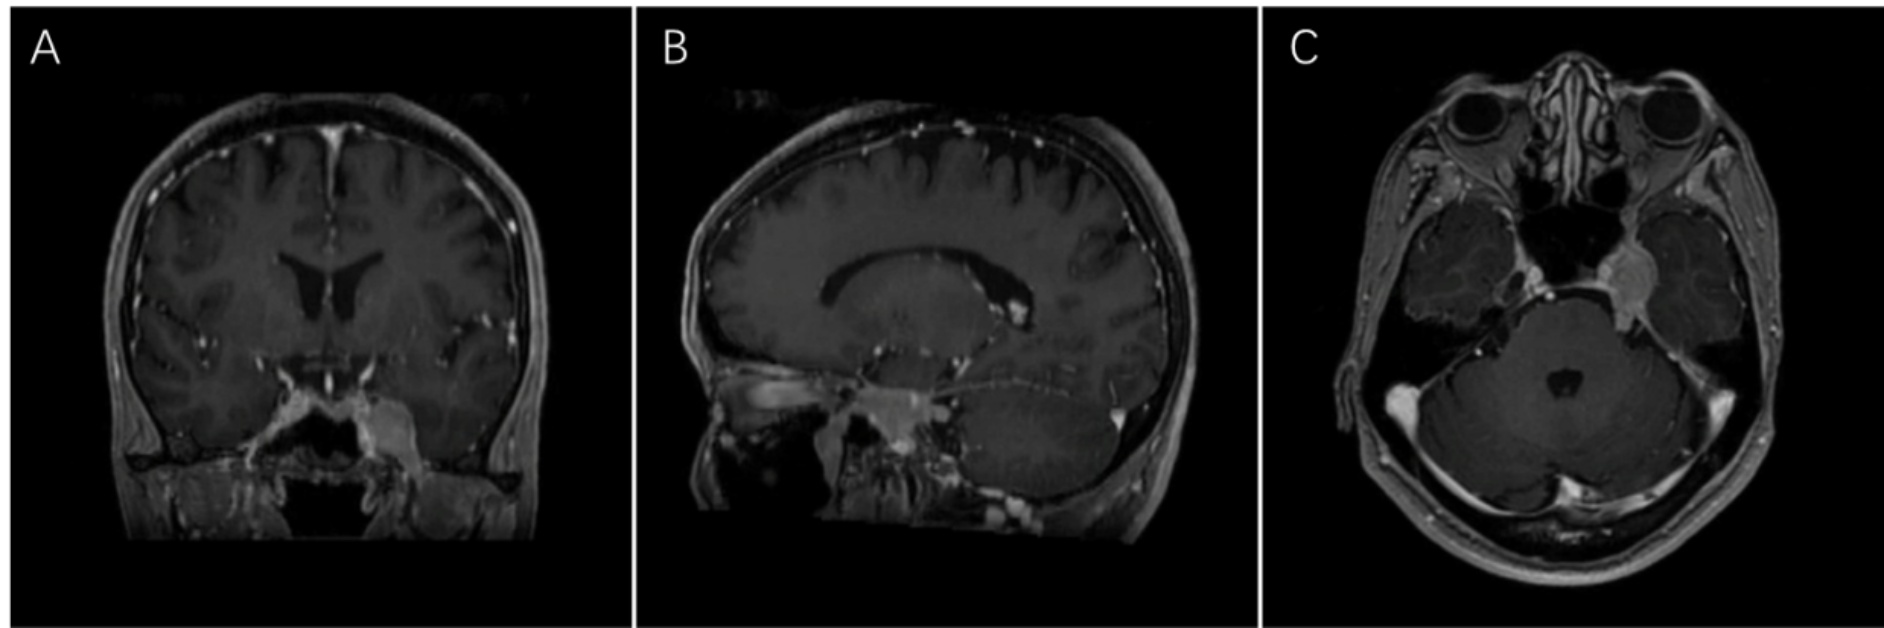

患者为51岁女性,主因左侧三叉神经支配区麻木、疼痛和左侧面部抽搐3个月前来就诊。2025年3月4日就诊于当地医院,予以口服卡马西平对症治疗,疼痛稍有缓解。完成相关检查后,患者接受了“三叉神经节球囊压迫术”,但症状未明显改善。2025年5月9日进行的脑部磁共振成像(MRI)平扫及增强序列显示,左侧鞍旁存在颅内外沟通性肿瘤,提示为脑膜瘤,鉴别诊断为神经源性肿瘤(图1)。随后,患者被转诊至我院神经外科进一步诊治。患者既往病史无特殊,无重大既往疾病。相关体格检查结果:左侧三叉神经第二、三支分布区的痛觉、温度觉、粗触觉及精细触觉减退;左侧眼睑闭合无力;粗略测量显示左耳听力下降;左侧咬肌肌力减弱;眼球运动无明显受限;颈部、锁骨下及腋窝未触及肿大淋巴结。相关实验室检查:血常规:淋巴细胞绝对值1.5 × 109/L,淋巴细胞相对值28.6%;颅脑核磁平扫 + 增强(2025-05-09日)提示:左侧鞍旁沟通性肿瘤病变。

(A)⁓(C) 肿块向前下方和后方延伸,穿过眶下裂、圆孔、卵圆孔、舌下神经管以及内耳道,部分突入颞下窝;并环绕左侧三叉神经和面听神经复合体,并部分膨入翼腭窝。其大小约为1.7 × 2.0厘米。

Figure 1. Preoperative contrast-enhanced magnetic resonance imaging (CE-MRI)

1. 术前增强磁共振成像

影像学特征:MRI显示鞍旁不规则肿块影,肿块分别经眶下裂,圆孔、卵圆孔、舌下神经管及内听道向前下、后生长,部分突入颞下窝,左侧三叉神经及面听神经受包绕,部分凸入翼腭窝,增强呈明显均匀强化,可见鼠尾征。核磁提示占位明确,具有脑膜瘤的特点。术后病理提示:弥漫性大B细胞淋巴瘤。在核磁增强中PCNS-DLBCL的特征是均匀的对比增强和清晰的边界,病灶周围血管源性水肿很常见,T2加权MRI上的低信号和弥散加权成像(DWI)上的弥散受限是PCNS-DLBCL的其他特征,但这并不能确保PCNS-DLBCL的诊断。极少数情况下,PCNS-DLBCL可能表现为颅神经或神经根神经的轻微局灶性异常或局灶性脑膜强化[15]